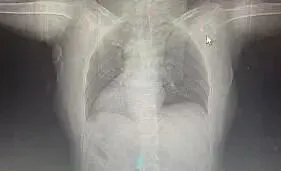

患者为61岁女性房颤患者,经CT、经胸及经食道心脏超声检查确诊为镜像右位心、右位主动脉弓罕见心脏畸形(发病率约十万分之一)。经科室讨论及与麻醉科、心脏大血管外科多学科会诊(MDT)后,决定在深度镇静保障下行三维引导的Farapulse PFA术。此为国内首例针对右位心患者实施的房颤PFA手术。

患者1镜面右位心影像图像